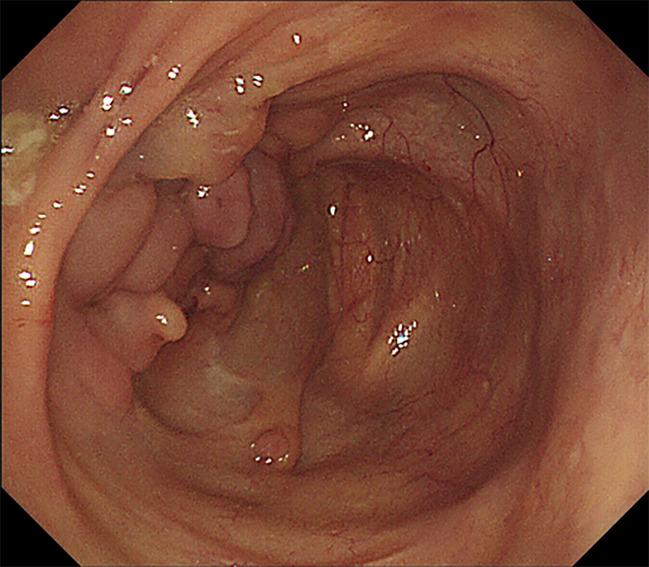

Colonoscopy is essential for the diagnosis of intestinal Behcet's disease (BD), which is characterized by a typical oval-shaped ulcer in the ileocecal region. However, potential risks of colonoscopy have rarely been reported.

Herein, we describe a patient with intestinal BD who presented with decreased oxygen saturation and shortness of breath during a diagnostic colonoscopy. Bilateral pneumothorax, pneumomediastinum, pneumoperitoneum, pneumoretroperitoneum and subcutaneous emphysema of the neck, chest, abdomen, back and scrotum were confirmed by computed tomography scan. The sudden change in condition was considered to be associated with iatrogenic bowel perforation. After receiving closed thoracic drainage and conservative therapy, the patient was discharged in stable condition.

结肠镜检查对于诊断肠道白塞病(BD)至关重要,肠道白塞病的特征是在回盲部有典型的椭圆形溃疡。然而,结肠镜检查的潜在风险鲜有报道。

在此,我们描述一名肠道BD患者,其在诊断性结肠镜检查期间出现氧饱和度下降和呼吸急促。计算机断层扫描证实存在双侧气胸、纵隔气肿、气腹、腹膜后气肿以及颈部、胸部、腹部、背部和阴囊的皮下气肿。病情的突然变化被认为与医源性肠穿孔有关。在接受闭式胸腔引流和保守治疗后,患者病情稳定出院。